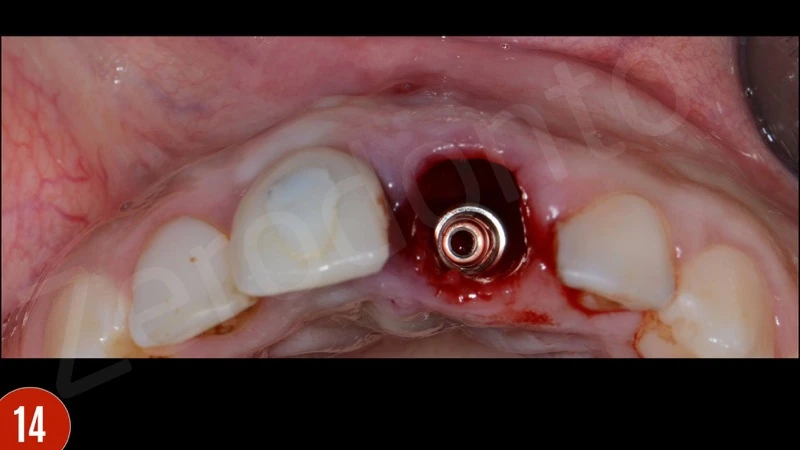

Sau khi nhổ răng, mô hạt đã được loại bỏ cẩn thận. Khoan xương phía khẩu cái cung cấp sự ổn định chính và đặt phục hình tạm thời. Để bảo vệ các đường cong phía môi, khoảng trống giữa bản xương phía môi và implant được ghép với xương bò khử khoáng. Phục hình tạm thời được gắn vào implant tại lực torque 15 Ncm.